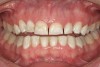

Figure 15  Patient demonstrates wear on deciduous molars increasing the risk of bruxing as an adult. Another explanation may be the triad. Constricted dental arch, crowded lower anteriors, and a deep bite with a lifetime of airway-related issues. GERD history coupled with erosive wear on teeth.

Figure 15